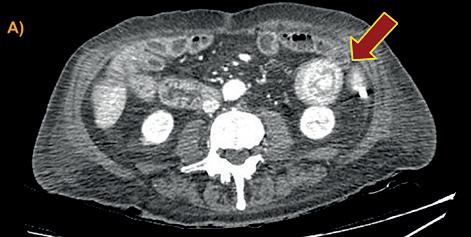

FIGURA 2. Tomografía de abdomen y pelvis con contraste EV: Se evidencia invaginacion intestinal (Signo de donut o escarapela) en asa correspondiente al yeyuno proximal, en cuya porción distal impresiona existir una lesión de contornos lobulados con refuerzo considerable post-contraste que podría corresponder a la cabeza de la misma y estar en relación a un pólipo pediculado. Mide 3 cm. en su diámetro mayor. No se observa una ostensible dilatación de la luz proximal. Los planos grasos mesentéricos tienen aspecto conservado A)- B)-C).Signo de la salchicha o pseudoriñón. Servicio de Tomografía, Departamento de Imágenes, Hospital de Clínicas “Jose de San Martin” [Av. Córdoba 2351, CABA].

(12/21) con posterior colocación de stent y múltiples episodios de hemorragia digestiva alta posteriores, que requirió internación (2022) por shock hemorrágico. Se realiza tomografía con de abdomen y pelvis con contraste endovenoso donde se constata intususcepción intestinal de porción proximal de yeyuno. (Figura 2)